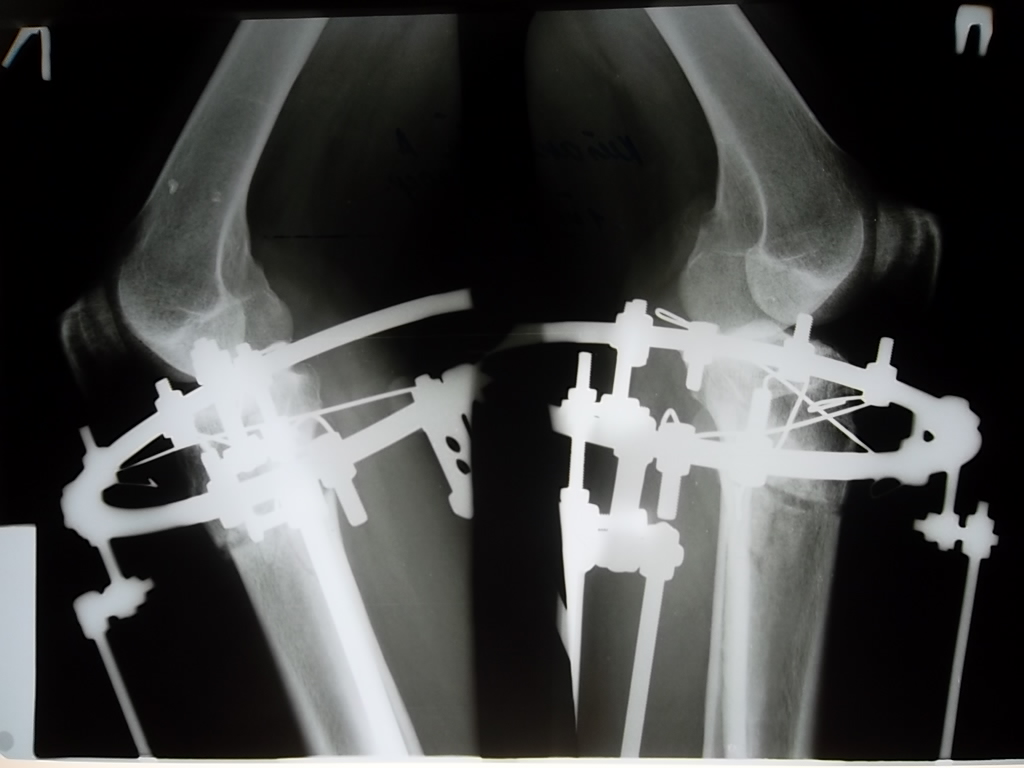

Контрольный рентген-снимок сделали, Николай Николаевич сказал, что все ок у нас.

Ягодуля, вчера нам убрали по одному штырю снаружи, слева и справа. Сегодня уберут оставшиеся штыри полностью, т.е. будем ходить только с кольцами. Не будет никакой опоры, придерживать ничего не будет. Страшновато. 094f316296.gif Если подробно, то вот так.

Дата операции 06.03.2013г.

Дата снятия аппаратов 18.06.2013г.

Срок лечения 102 дня.

рентгеновские снимки за 2 недели до снятия аппаратов.